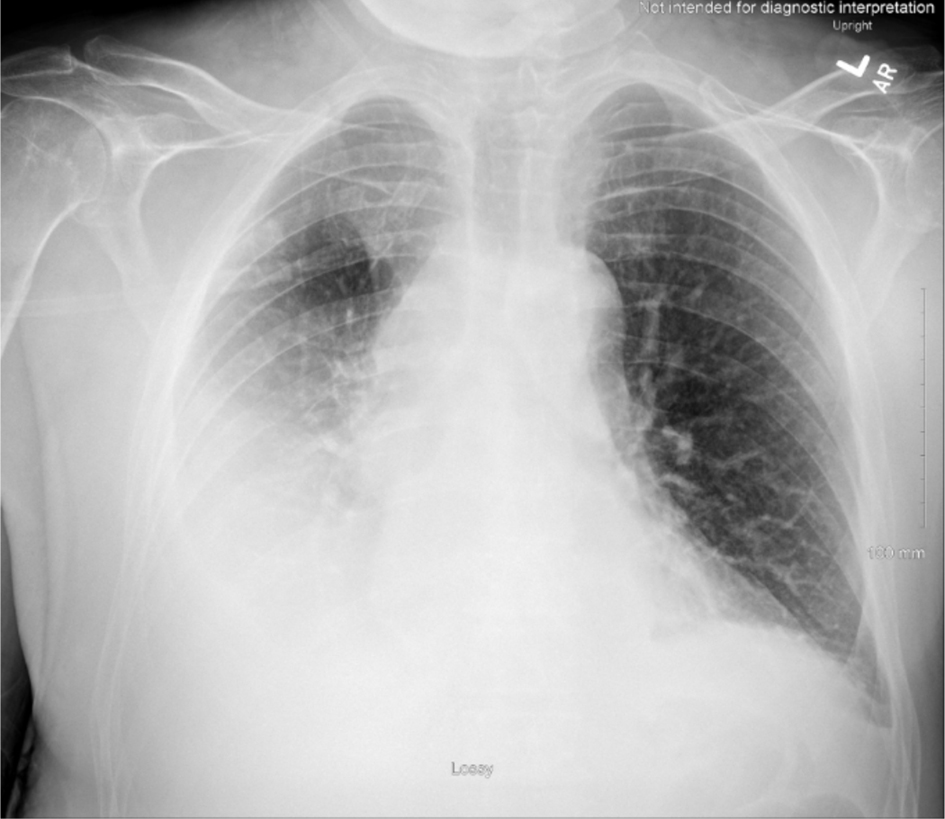

As the patient’s respiratory rate and SpO2 levels improved, he returned to inpatient services to complete three more radiation sessions. Even with the supplemental oxygen given, patient’s pleural effusion inevitably worsened (Fig. 4), prompting to multiple thoracenteses procedures and placement of the PleurX catheter. The patient later developed new-onset atrial fibrillation with rapid ventricular response (RVR), returning to the ICU where he was placed on amiodarone hydrochloride and apixaban. As the patient’s pericardial effusion worsened, a pericardiocentesis procedure was performed and biopsied for a malignant cytology confirmation. A pericardial window was not recommended per cardiothoracic surgery due to patient’s concerns of continuing radiation treatment, suspicions of atrial fibrillation secondary from the radiation therapy, and large tumor invading SVC.

Click for large image

Figure 4. Chest X-ray obtained on hospital day 14, depicting an increase of right pleural effusion. Trace left pleural effusion and bibasilar areas of consolidation that may reflect atelectasis.